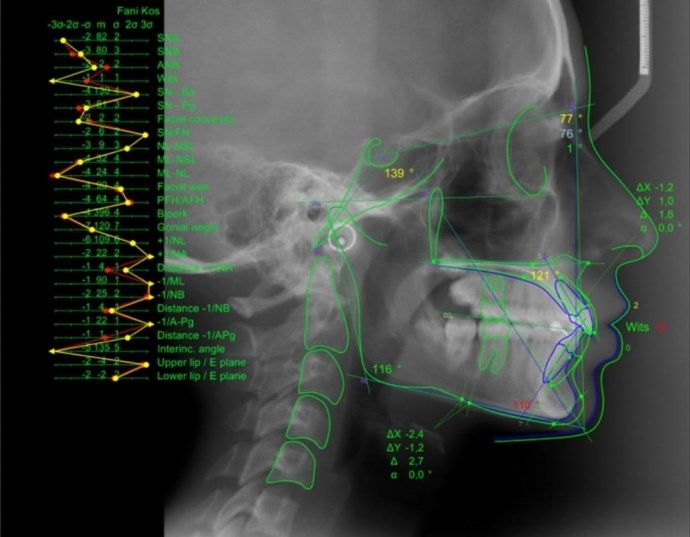

Haga informes de sus radiografías, cree proyecciones de crecimiento del cráneo, planes de tratamiento, predicciones y simulaciones, además, estudie el resultado general de su tratamiento.

Automatice su trabajo, gracias a la inteligencia artificial, ahorre ese tiempo que tanto necesita en la consulta y evite ese trabajo tedioso de realizar cálculos manuales.